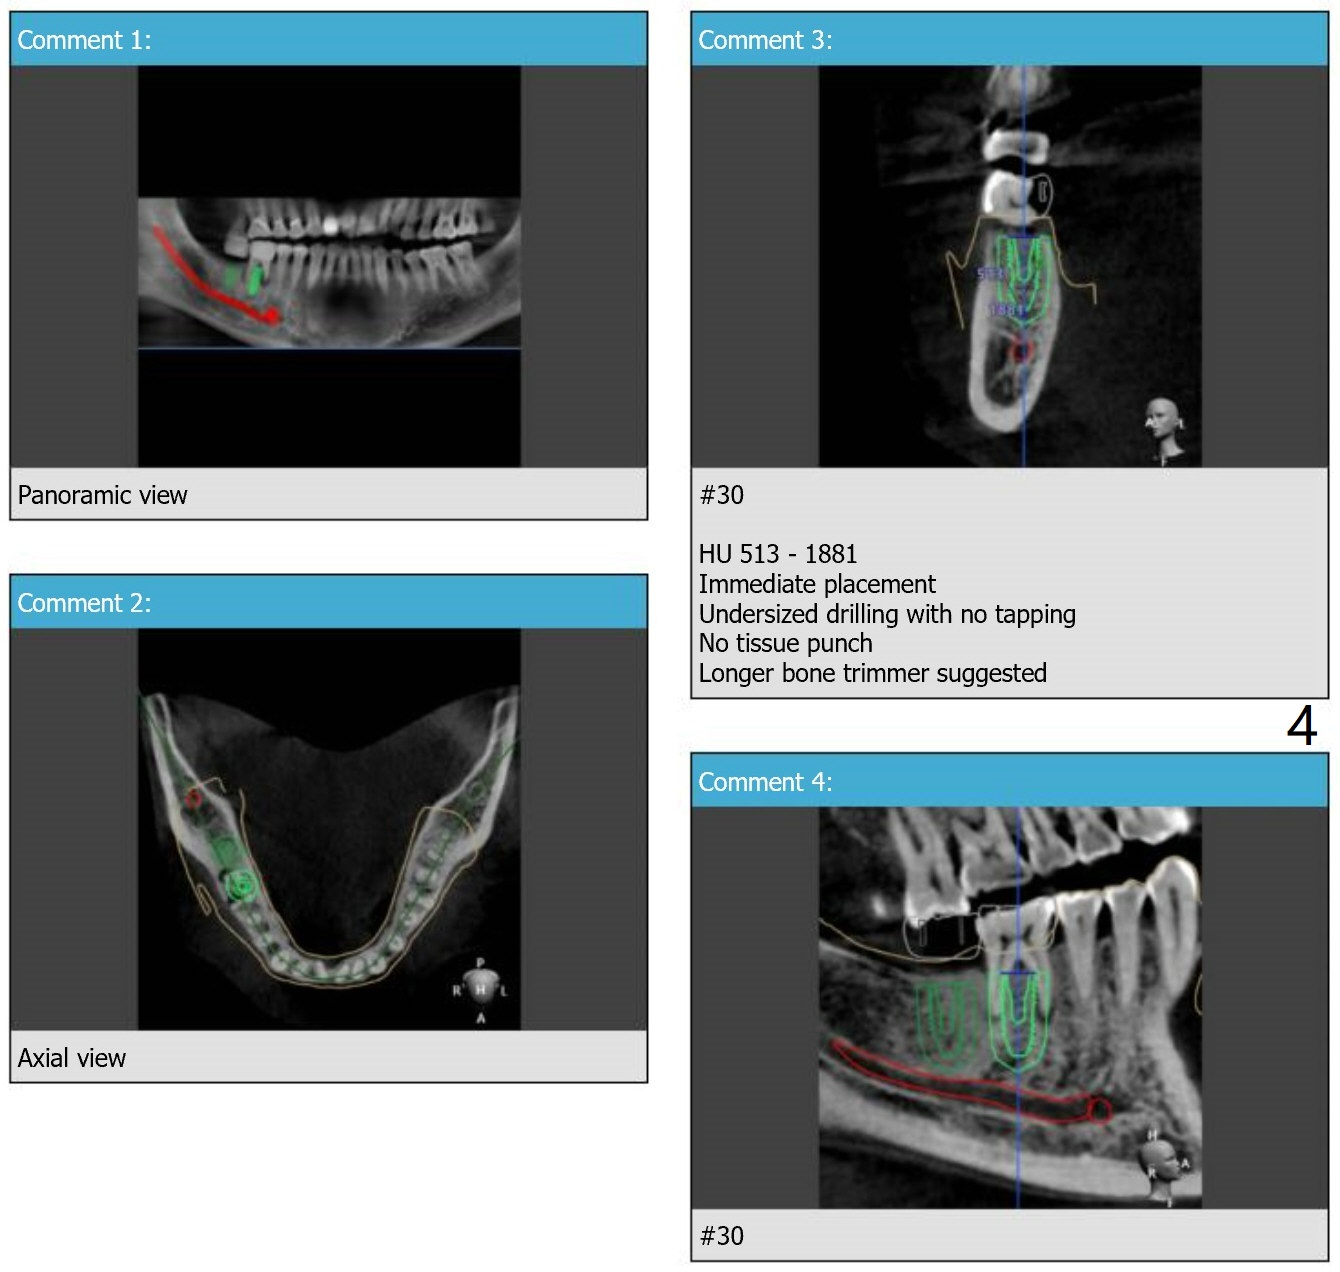

Return to Lower Molar Immediate Implant, Prevent Molar Periimplantitis (Protocols, Table), Trajectory, Clindamycin Xin Wei, DDS, PhD, MS 1st edition 11/30/2018, last revision 01/15/2019